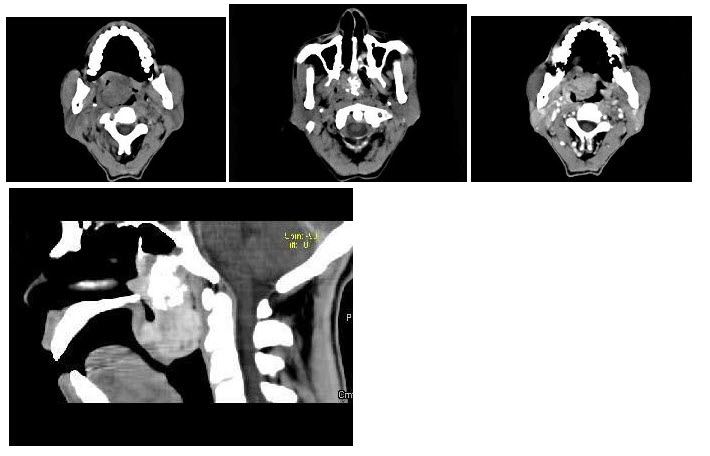

8、单项选择题

男,31岁,感左坐骨区胀痛,无发热,结合所提供的图像,最可能的诊断是()

11、单项选择题

青少年患者,臀疼,最可能的诊断为()

14、单项选择题

男,48岁,胃癌术后1年,未化疗,CT检查如图所示,最可能的诊断为()